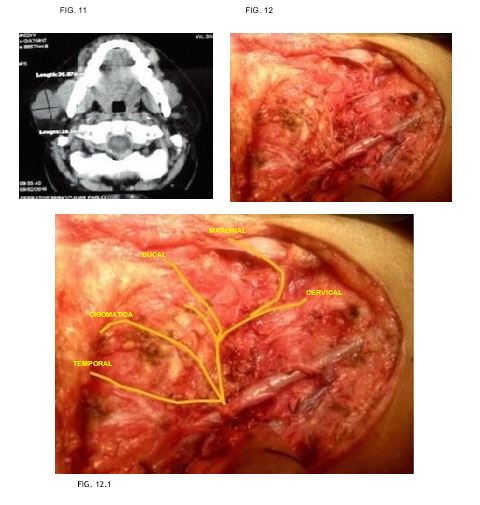

Caso 6: masculino de 23 años de edad, sin antecedentes de importancia, con tumor parotídeo izquierdo sometido a parotidectomía supraneural resultando en adenoma pleomorfo. (FIG. 11-12)

Caso 7: femenino de 62 años de edad, antecedente de hipertensión arterial, con tumor parotídeo derecho de 7 x 6cm, resultando en adenoma pleomorfo. (FIG. 13-14)